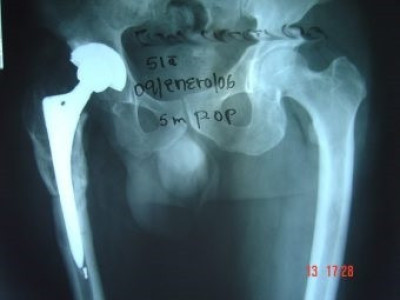

Prótesis Total de Cadera

Envíado por Dr. Ricardo Antonio Gómez G.